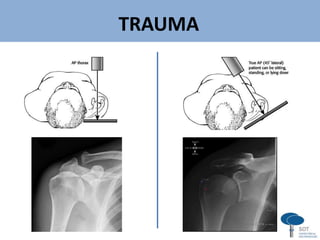

Série Trauma de Ombro (Neer)

AP verdadeiro

(de Grashey)

Perfil escapular Axilar

Outras formas de axilar...

TRAUMA

v

“Velpeau View” por

Bloom e Obata